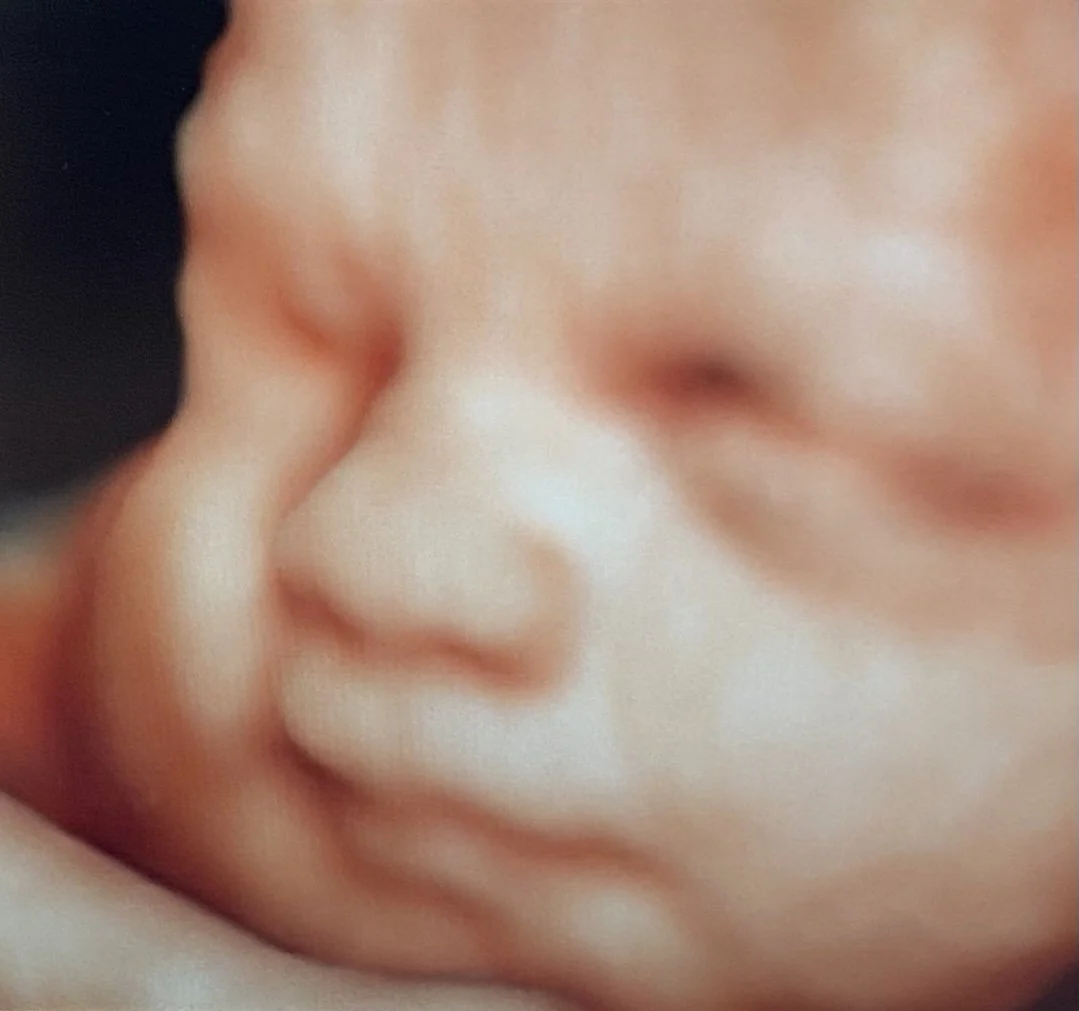

Our state-of-the-art technology (GE Voluson Swift) is one of the most popular ultrasound machines for obstetric scanning. It features class leading 4D imaging as well as proprietary GE efficiency technologies. 3D/4D imaging modes, CrossXBeam and Speckle Reduction imaging assist with excellent accuracy.

ScanSanctuary Client Scan Examples